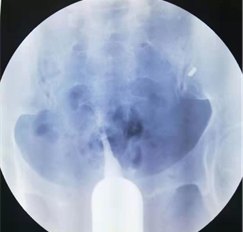

这是2年前的一个病例。一位广州市荔湾区桥中街村民邓XX,43岁,20年前第一胎生儿子后结扎。开放二胎后做输卵管吻合术,术中腹腔镜通液显示输卵管不通。术后第3个月找我做造影。我第一次做造影时造影导管插入宫颈浅进入不了宫腔,球囊固定不了造影管。我就用探针探测看看,探针只能进去宫腔3.5厘米,就在宫颈外口注造影剂,显示宫腔呈一长条状,形态同一段探针相仿,见图像1。我虽然是放射介入科医生,但是我是妇科生殖专业博士,在读妇科博士前,还专门进修妇科6个月,做过宫腹腔镜手术,插造影管对我来说是很简单的手术,基本上没有插不上造影管。做不了造影。但是,为诊断清楚,就没收费用,预约第二天请广州市红会医院原妇科主任,著名妇科腔镜专家陈燕辉主任出诊时,请陈主任插管再做一次造影。第二天,陈主任插造影管后,也固定不了造影管,就用探针探测宫腔,考虑重度宫腔粘连,宫腔近封闭,就用探针分离一下宫腔。我又在宫颈外口注入造影剂进行造影,显示宫腔近呈单叶片状,形似单角子宫,见图像2。然后追问病史,患者才讲10年前子宫大出血,做一次刮宫后再也没有月经。第二个月陈主任门诊行宫腔镜探查术证实重度宫腔粘连。重度宫腔粘连输卵管开口封闭,不管是做试管还是自然怀孕都不行,需要处理宫腔粘连才行。由于患者年纪大,和家属商量后就放弃再怀孕。因此,就没有处理宫腔粘连。符合宫腔粘连对于没有生育要求和没有痛经等不适者可以不手术的治疗原则。

结扎图1.png

图一